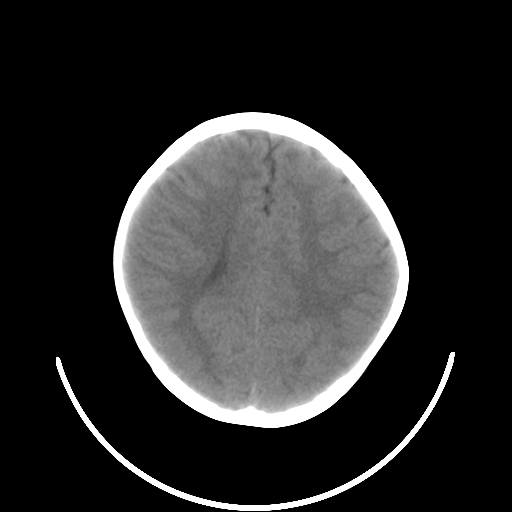

以下是引用深泽交通医院在2009-10-16 8:25:00的发言:[br]右眼环出血伴异物

以下是引用卜一在2009-10-16 15:01:00的发言:[br]右眼球挫裂伤伴异物!

以下是引用拾荒者在2009-10-17 18:38:00的发言:[br]鼻面部皮下积气,右侧睑缘及眼球壁高密度异物影,左侧眼球壁晶状体内侧缘处是圆形低密度影。低密度异物?应提请眼科医生注意。